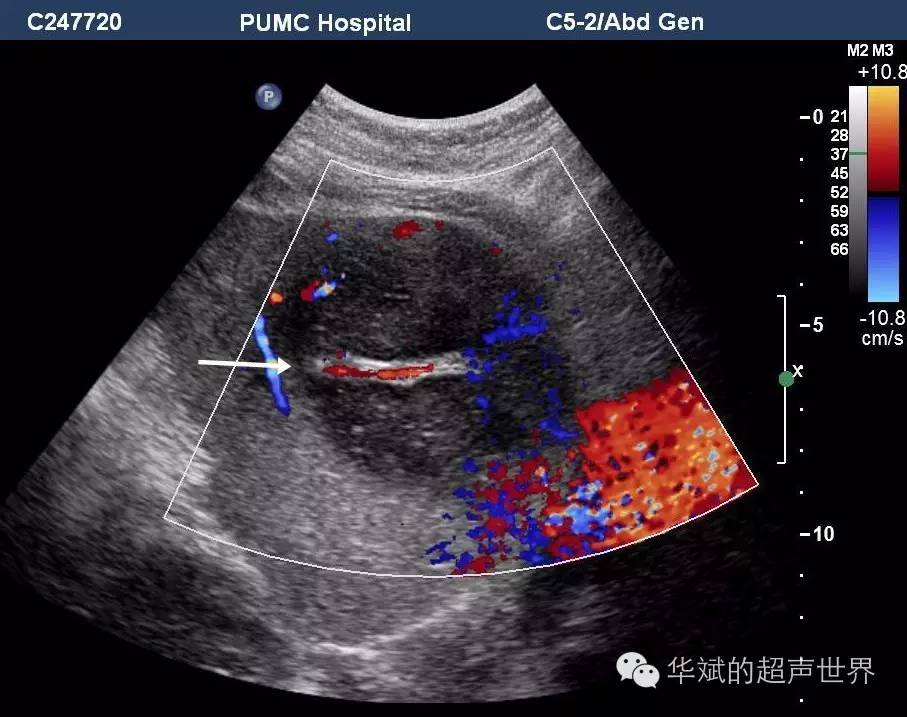

肝脏淋巴瘤之血管漂浮征

907x717 - 76KB - JPEG